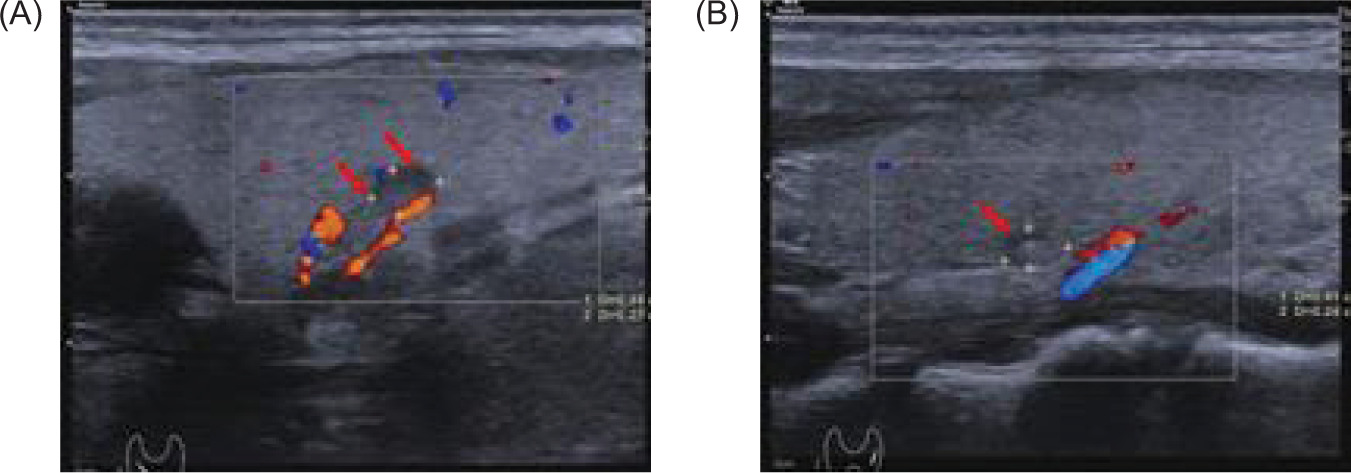

Brain MRI revealed a cystic mass in the right cerebellar hemisphere measuring approximately 40 mm (Figure 6). Thyroid color Doppler ultrasound revealed solid and cystic nodules in both thyroid lobes (C-TIRADS: Category 3) (Figure 7). His fasting blood glucose level was 20.6 mmol/L. On November 29, 2024, he was treated with intensive insulin therapy, and his antidiabetic regimen was adjusted to injection aspart insulin, 4 units tds daily before meals and injection degludec insulin, 5 units once daily at night. The patient’s fasting blood glucose stabilized at 4.5–5.0 mmol/L, and postprandial blood glucose stabilized at 6.0–8.0 mmol/L in 3 days before discharge, and his clinical manifestations, such as polydipsia and weakness in the lower limbs, decreased significantly.

Figure 6: Magnetic resonance imaging (MRI) of the brain reveals a cystic mass in the right cerebellar hemisphere, approximately 40 mm in size (red arrow); (A) sagittal position, and (B) flair view.

Figure 7: Thyroid color Doppler ultrasound shows bilateral cystic and solid thyroid nodules with clear boundaries, measuring (A) about 0.44×0.27 cm (right) (red arrow), and (B) 0.41×0.24 cm (left) (red arrow) (C-TIRADS: category 3).